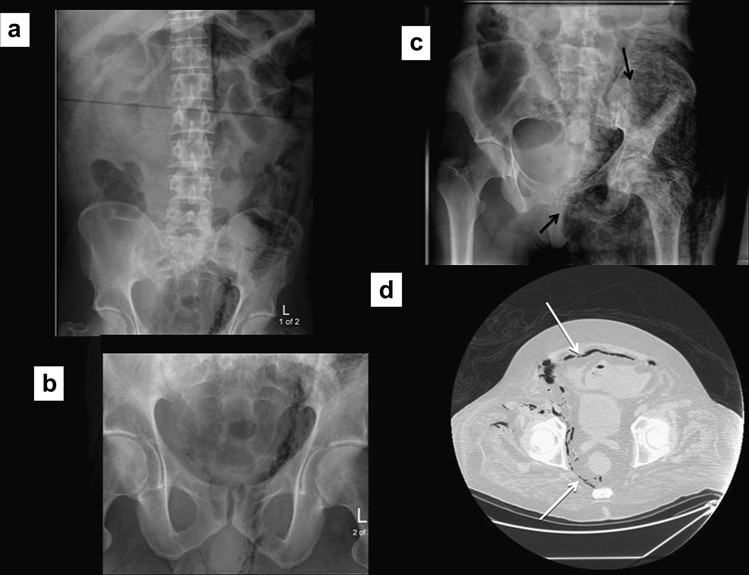

Nguyên nhân dẫn tới tắc ruột non, đặc biệt là thoát vị, đôi khi có thể nhận ra trên phim X quang và nên được tìm kiếm một các hệ thống trong tắc ruột. Điều này yêu cầu phim X quang bụng phải bao phủ cả vùng bẹn vì đó là vị trí hay thoát vị gây tắc ruột nhất. Thoát vị bịt hoặc thoát vị rốn đôi khi tạo nên các mẫu hình khí gợi ý trên phim X quang, do đó chụp cắt lớp vi tính kéo xuống mức thấp hơn để đánh giá chi tiết (Hình 2). Tắc ruột do sỏi mật và các khối ổ bụng gây tắc ruột đôi khi cũng có thể được phát hiện.

Hình 2. Tắc ruột non do thoát vị nghẹt lỗ bịt. (a) Nhiều quai ruột non giãn. Lưu ý có một ít khí dưới dây chằng bẹn ở lỗ bẹn phải (b,c) Chụp CT cho thấy một quai ruột ở giữa cơ bịt trong và cơ bịt ngoài, xác định thoát vị bịt bên phải gây tắc ruột.